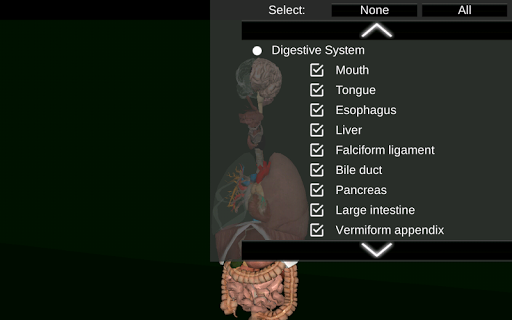

* Травна система, включаючи шлунок, тонку кишку, товсту кишку та анімацію цієї системи.

* Приховати або показати інформацію.

* Додано можливість приховати органи.

* Додана опція для приховування органів.

* Додана можливість приховати органи.

* Додана можливість показати контур тіла. * Додано 6 кнопок, що групують різні системи (травлення, репродуктивні, дихальні та ін.). * Внутрішні оптимізації для підвищення продуктивності. * Виправлена проблема з органом "Spleen".